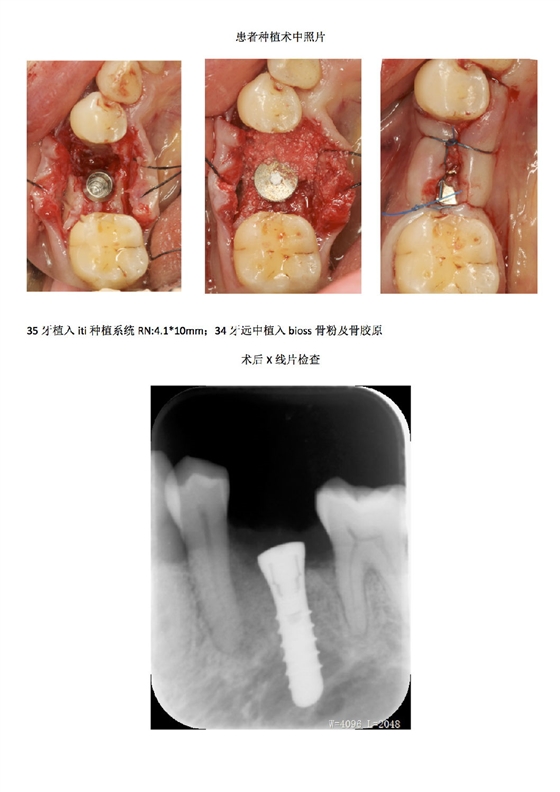

首頁牙周防治 牙周病患者種植治療+鄰牙GTR病例匯報(bào)

牙周病患者種植治療+鄰牙GTR病例匯報(bào)